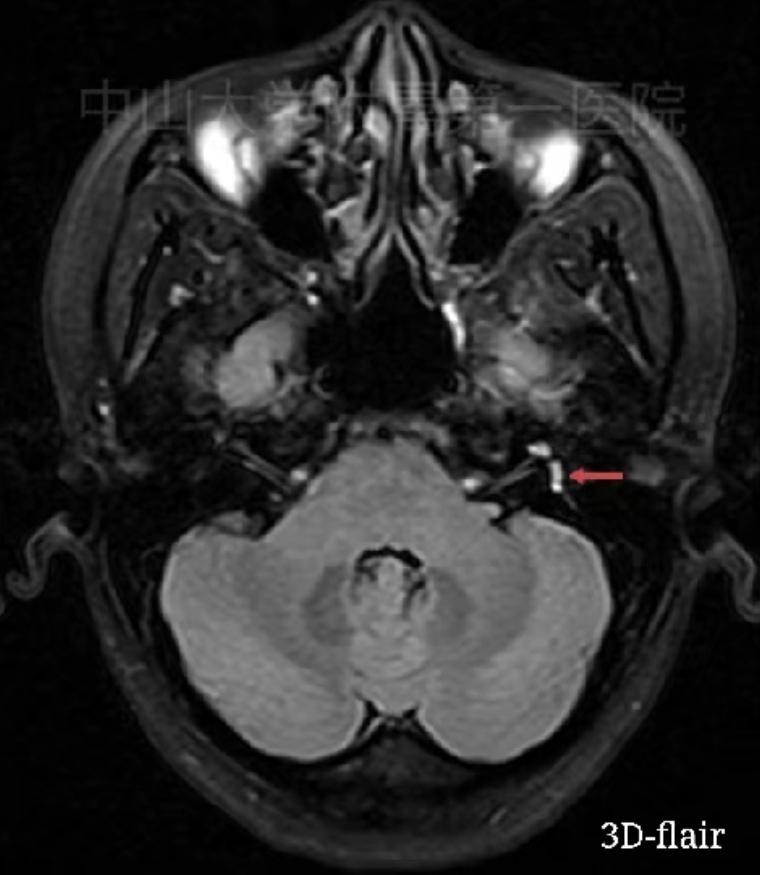

据文献报道,80%以上突聋病因不明确,可能病因如病毒感染、自身免疫、内耳微循环障碍等,全聋型突聋常见病因则是内耳微循环障碍,如内耳血管痉挛、栓塞甚至出血。由于内耳供血血管细小,目前磁共振影像技术还无法显示内耳血管是否栓塞,近几年,利用磁共振特殊影像系列,可以发现内耳出血,显示部分突聋发病与内耳出血密切相关。